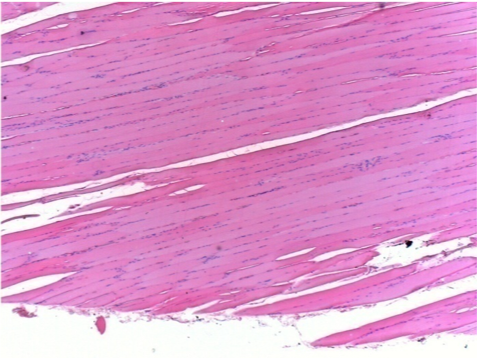

3 months after Endopeel Injection

3 months (D90)after Endopeel Injection 0.1ml in the right pretibial muscle.

L : Control-100xD90

R:100xD90